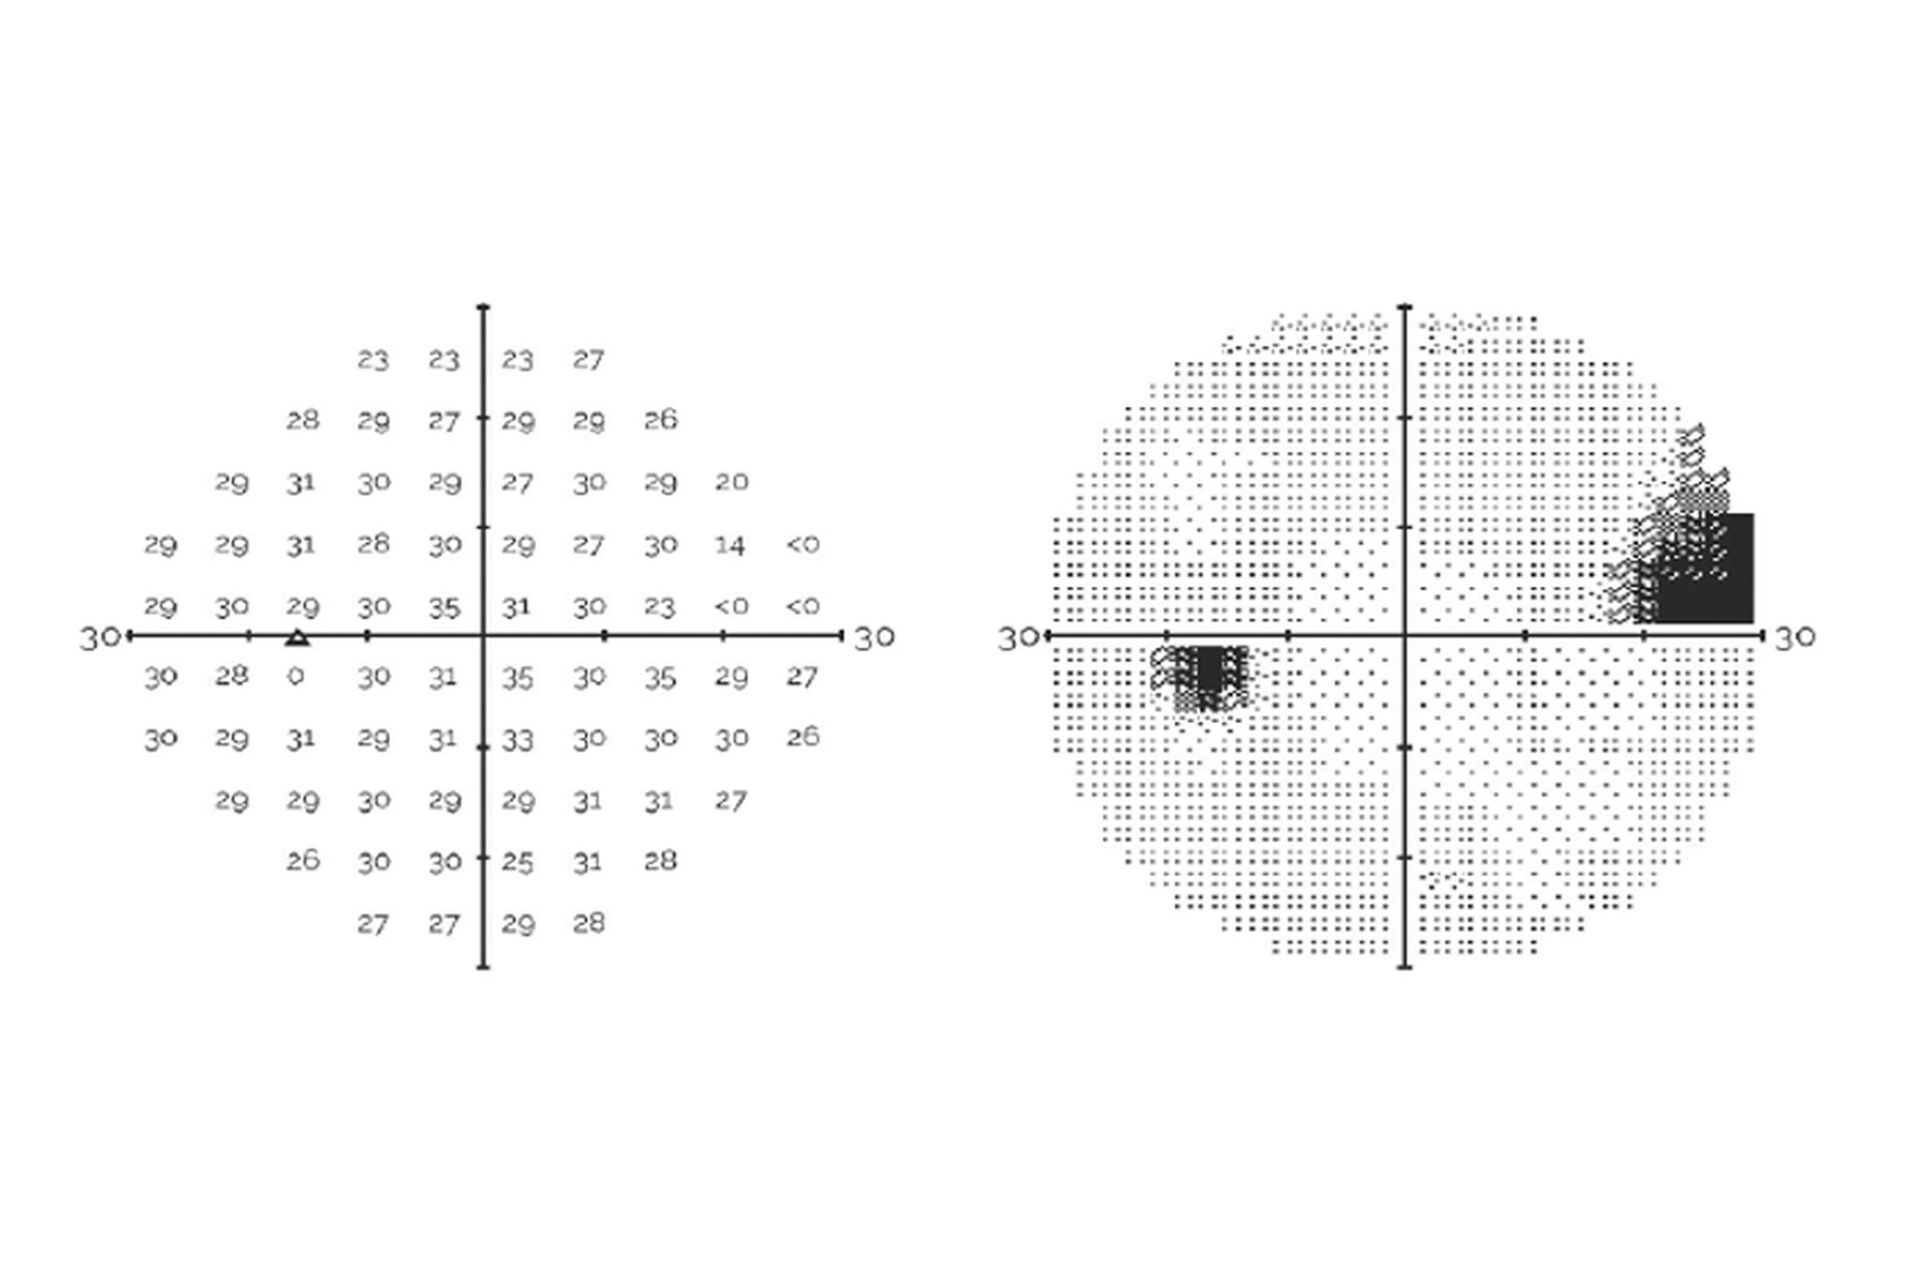

Evaluation of a Virtual Reality-Based Device (RVF100) for Visual Field Testing: A Comparison with the Humphrey Visual Field Analyzer

Compares VR perimetry results from the RetinaLogik RVF100 with the gold-standard Humphrey Visual Field Analyzer, showing strong alignment across key visual field metrics and supporting its use as a reliable alternative in clinical practice. (Under Review)

Inter-test Comparability of a Novel VR Perimetry Device with the Humphrey Visual Field Analyzer

Evaluates the alignment between VR perimetry results and the gold-standard HFA, analyzing multiple visual field metrics to determine clinical equivalence. (COS 2024)

Advancing Ocular Diagnostics: A Comparative Study Between the RVF100 Portable Virtual Reality Device and the Humphrey Visual Field Analyzer for Glaucoma Suspect Assessment

An ARVO 2024 study comparing the RetinaLogik RVF100 to the Humphrey Visual Field Analyzer in glaucoma suspect evaluations found strong correlation across all key metrics (MD, PSD, MS), with performance comparable to gold-standard testing—supporting VR perimetry as a validated, portable, and cost-effective alternative. (ARVO 2024)